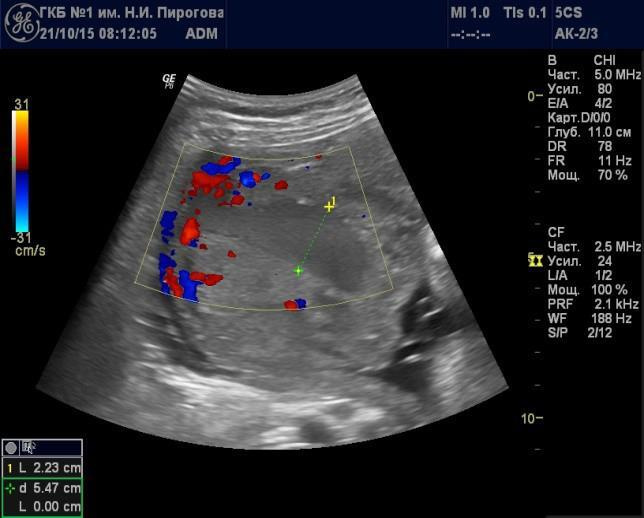

Участки расширения МВП могут быть различной формы (округлой, овальной, неправильной) и размеров (диаметром от нескольких миллиметров до нескольких сантиметров (Рис. 12). Их субхориальное расположение может приводить к выбуханию хориальной пластинки в амниотическую полость, характер которого может незначительно меняться в процессе проводимого исследования.

Расширение участков МВП при плацентографическом исследовании во второй половине беременности (после 20 нед.) регистрируется с частотой от 2 до 18%. Их выявление в количестве не менее 3-х и размерами не менее 20 мм трактуется как регистрация «плацентарных озер» [34]. Уместно подчеркнуть, что выраженное расширение МВП плаценты приводит к ее увеличению, о чем можно судить по ее толщине.

Рис. 12. Беременность 34 нед. Расширение межворсинкового пространства, связанное с венозным оттоком в режиме цветового допплеровского картирования (направление низкоскоростного движения крови было установлено визуально в режиме реального времени).

В зависимости от размеров участка расширения МВП и скорости движения в нем крови ее течение может быть отмечено визуально при серошкальном режиме исследования. Вероятность визуализации повышается при значительном расширении участки МВП и относительно высокой скорости кровотока в нем (> 6 мм/сек). Упрощает регистрацию движения крови в МВП применение ЦДК. Использование высокочувствительной УЗ аппаратуры позволяет определить в МПВ очень медленный (около 1-5 мм/с) ламинарный поток крови. Не следует забывать, что возможности регистрации тока крови в расширенном МВП зависят и от угла между его направлением и направлением допплеровского «луча». В ряде случаев подтвердить движение крови в МВП можно лишь с помощью режима энергетического допплеровского картирования, как более чувствительного к низким скоростям кровотока, а также менее «уголзависимого» по сравнению с цветовым. Так, на рис. 13 проиллюстрирована возможность регистрации кровотока в расширенном участке МВП, расположенного в центральной части плаценты.